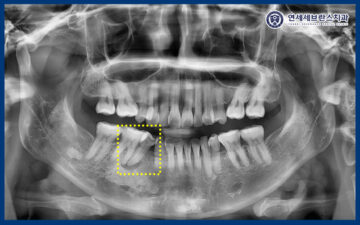

확인해 보니,

오른쪽 아래 두번째 작은 어금니가

검붉은 색으로 변색이 되어있었는데요.

곡반정동치과

24.08.01

자세한 확인을 위해

엑스레이 사진을 촬영해 보니,

치아 뿌리 끝 염증을

관찰할 수 있었습니다.